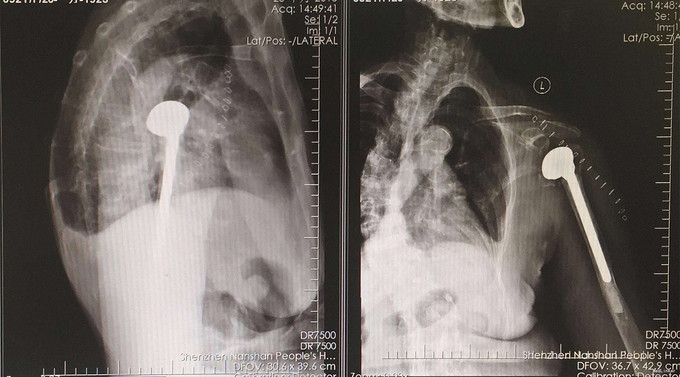

完善检查后行,左肩关节人工肱骨头置换术。手术过程一小时40分钟。术后第三天出院。

出院后两周,四周随访,患者手术切口愈合可,患者能够自行端碗吃饭。 请教各路大侠,对于骨质疏松较明显且高龄的老年人,是否还应该尝试内固定手术呀,这个我也很纠结。